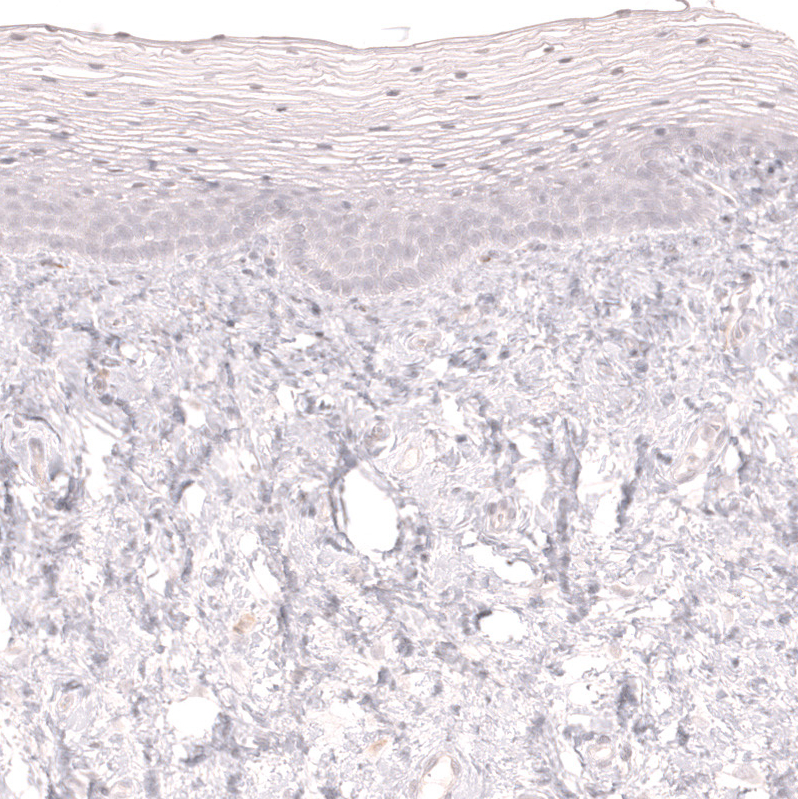

Immunohistochemistry analysis in human tonsil and skeletal muscle tissues using AMAb91996 antibody. Corresponding LAG3 RNA-seq data are presented for the same tissues.